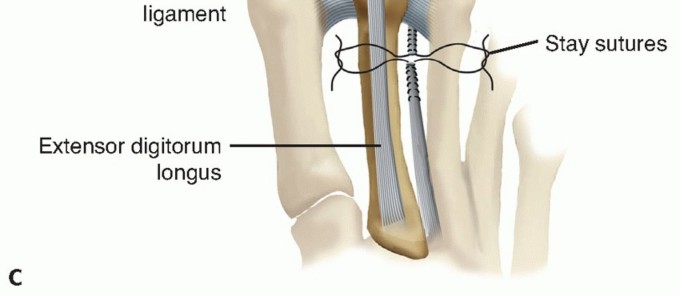

After two 4-0 stay sutures have been placed longitudinally into the tendon 4 cm proximal to the MTP joint, the tendon is transected between these two sutures (TECH FIG 3A).

TECH FIG 3 • A. Stay suture placement along the EDB tendon and transaction point identified by dashed line between the two sutures. The EDL tendon is also shown after Z-lengthening. B. Transfer of distal EDB stump plantar to transverse metatarsal ligament and lateral to second metatarsal. (continued)

The passed distal limb of the EDB is then tensioned and secured by a direct end-to-end tendon repair to the proximal stump, with the joint held in congruity (TECH FIG 3C).

- TECH FIG 3 • (continued) C. End-to-end repair of the EDB tendon with the toe pinned in a corrected position. The Z-lengthened EDL tendon is also shown following repair.